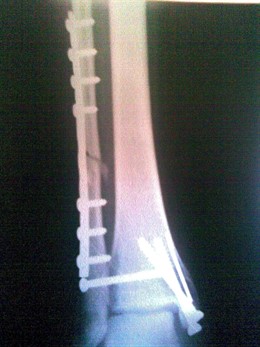

Radiografia, Hueso

Radiografia, Hueso - EUROPA PRESS